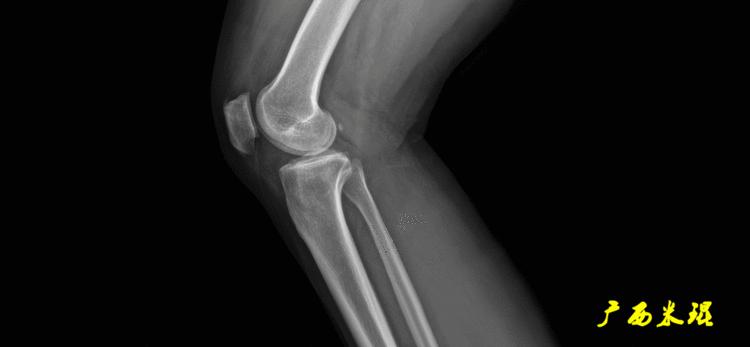

(2)膝关节中心

膝关节中心点常用的有5个不同的定位方法,分别是股骨髁中点、股骨髁间窝顶点、膝关节间隙水平软组织中点、胫骨髁间嵴中点和胫骨平台中点,我们可以根据具体情况来选用。